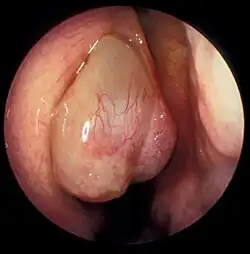

Nasal polyp in the middle meatus

Nasal polyp appearing in the middle meatus.

Nasal polyps can be seen on physical examination inside of the nose and are often detected during the evaluation of symptoms. On examination, a polyp will appear as a visible mass in the nostril.[5] Some polyps may be seen with anterior rhinoscopy (looking in the nose with a nasal speculum and a light), but frequently, they are farther back in the nose and must be seen by nasal endoscopy.[12] Nasal endoscopy involves passing a small, rigid camera with a light source into the nose. An image is projected onto a screen in the office so the doctor can examine the nasal passages and sinuses in greater detail. The procedure is not generally painful, but the person can be given a spray decongestant and local anesthetic to minimize discomfort.[13]